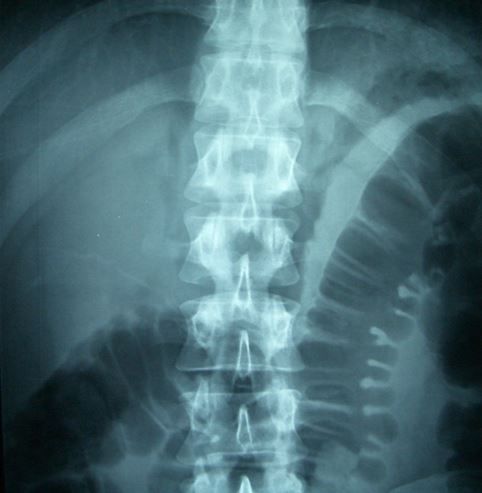

A 38-year-old man slips while rushing down hardwood stairs wearing socks and falls hard onto the stairs, injuring his back. He is having difficulty walking because of right-sided low back pain that radiates up his back and down to his thigh when he tries to stand.

On physical examination, vital signs are all normal except for the man’s blood pressure, which is elevated at 147/81 mm Hg, most likely a result of pain. His head and neck are nontender and atraumatic. His upper back is nontender, but his lower back is tender.

On spinal films, the lateral view findings are normal. The anteroposterior view is shown here. There is a fracture of the right lateral spinal process or the first lumbar vertebra.

Spinal fractures most often are caused by falls, motor vehicle accidents, and sports injuries. Unstable lumbar spinal fractures are more severe than stable fractures, typically involving 2 of the 3 spinal columns (anterior, middle, and posterior), and there is a significant risk of spinal cord injury. Stable fractures are extremely unlikely to be associated with spinal cord injury.

Case and image courtesy of Brady Pregerson, MD